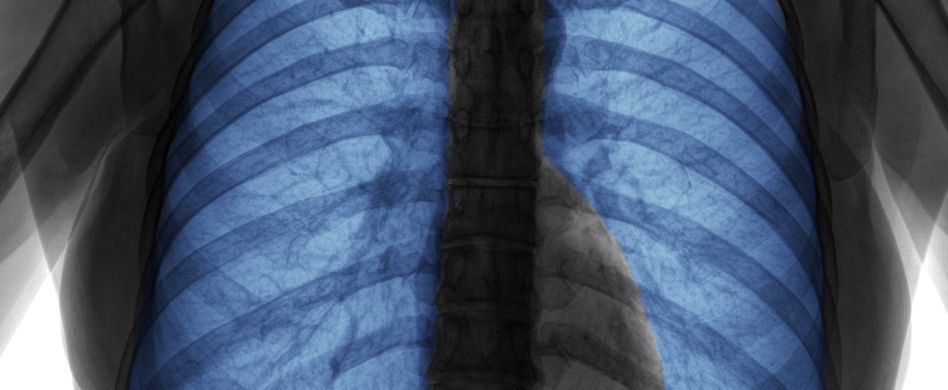

Lunge röntgen: Wann ein Röntgen-Thorax nötig ist und was der Arzt sieht

Lunge röntgen, auch Röntgen-Thorax genannt, hilft, Lungenkrankheiten im Frühstadium zu erkennen. Die Lunge selbst hat keine Schmerzrezeptoren. Husten, körperliche Erschöpfung sowie schleichender Luftmangel sind Warnzeichen, die ein Röntgen der Lunge notwendig machen.

Umgangssprachlich wird der Röntgen-Thorax einfach als „Lunge röntgen“ bezeichnet. Ein Röntgen-Thorax ist eine radiologische Untersuchung (Röntgen der Lunge) des Brustkorbs und der darin liegenden Organe wie Lunge, Herz, Rippen, Zwerchfell, Schlüsselbein und Gefäße. Der Röntgen-Thorax ist eine wichtige Untersuchung. Durch das Röntgen der Lunge können Lungenerkrankungen diagnostiziert und der Krankheitsverlauf überwacht werden. Auch nach Unfällen oder vor einer Operation ist der Röntgen-Thorax unverzichtbar.

Dias Röntgen der Lunge ist eine der am häufigsten eingesetzten radiologischen Untersuchungen. Beim Röntgen-Thorax dringen Röntgenstrahlen in den Körper ein und durchdringen die verschiedenen Gewebe, Organe und Knochen. Diese schwächen die Röntgenstrahlen unterschiedlich stark ab. Diese Unterschiede können auf Bildern dargestellt werden. Veränderungen im Lungengewebe lassen sich so feststellen. Tumorgewebe beispielsweise hat eine höhere Dichte als gesundes Lungengewebe. Auf dem Röntgenbild erscheint gesundes Gewebe dunkel, während das Tumorgewebe deutlich heller ist.